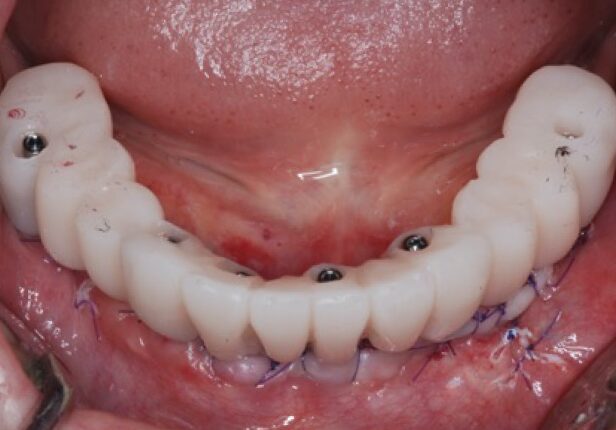

Mandibular Full case

Temporary Crown right after the placement (1st:: Shell)